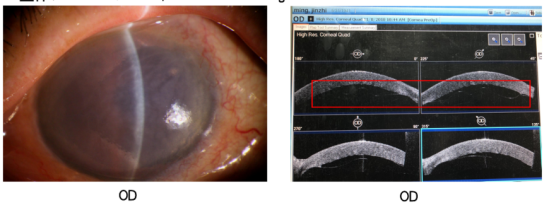

现病史:9天前于外院行右眼P+I术,现诉右眼视物模糊9天。

查体:视力HM/10cm(OD);眼压8mmHg(OD)

图片

诊断:右眼后弹力层脱离,右眼人工晶状体植入状态

治疗:右眼前房注气+后弹力层复位术;右眼二次前房注气;右眼三次前房注气